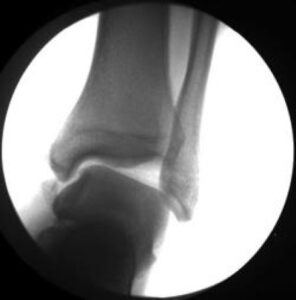

Ankle sprains are among the most frequent injuries affecting individuals of all ages and activity levels, and they are a leading cause of missed athletic participation. These injuries occur when the sturdy ligaments stabilizing the ankle are overstretched or torn. The severity of an ankle sprain depends on the number of ligaments affected and the extent of the damage.

In most cases, ankle sprains respond well to conservative treatments, such as applying ice, elevating the ankle, using over-the-counter pain relievers, and performing basic rehabilitation exercises. However, if swelling or pain persists for several weeks, or if bearing weight on the affected ankle becomes challenging, a medical evaluation may be necessary to rule out a severe sprain or fracture.

When symptoms fail to improve with non-surgical treatments, surgical intervention might be required to repair or reconstruct the damaged ligaments. Without proper care and rehabilitation, severe or untreated ankle sprains can lead to long-term complications, such as chronic pain, arthritis, or ankle instability, increasing the risk of recurrent injuries.